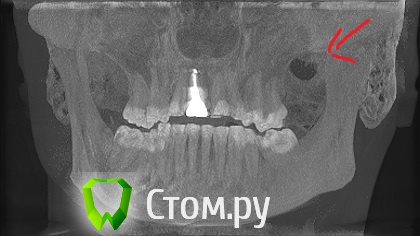

dr-krasnov Опубликовано 12 июня, 2014 Поделиться Опубликовано 12 июня, 2014 Вот это может болеть еще как . .. http://i047.radikal.ru/1406/cc/8c436bf06c72.jpg 5 Ссылка на комментарий

sergey765 Опубликовано 13 июня, 2014 Автор Поделиться Опубликовано 13 июня, 2014 спасибо вам огромное!!! вот этот снимок мне и нужен был. я его в программе искал и не мог найти. мне девушка показывала этот снимок. сказала что там инфекции дофига.. спасибо огромнейшее!!!! это получается КТ именно удаленного зуба и рядом с ним больного, правильно? тех которые на моём фото с телефона? если так, то я бы хотел спросить у вас совета... ничего там у меня сильно страшного нет? зуб этот больной не болит., он года 2 назад последний раз у меня болел.... и что с ним мне делать? лечить или удалять? возможно что это из-за него хреново заживает удаленный зуб?? и стоит ли вскрывать и чистить лунку удаленного зуба? Ссылка на комментарий

Bier Опубликовано 13 июня, 2014 Поделиться Опубликовано 13 июня, 2014 КТ у вас всех зубов, доктор лишь выделил нужный срез. Зуб этот надо лечить. Если лунка не заживает - ее надо почистить. 2 Ссылка на комментарий

sergey765 Опубликовано 13 июня, 2014 Автор Поделиться Опубликовано 13 июня, 2014 может у меня там вообще какой-нибудь рак... и крышку гроба уже пора заказывать... что допустим во это вот за фигня Ссылка на комментарий

dr-krasnov Опубликовано 13 июня, 2014 Поделиться Опубликовано 13 июня, 2014 (изменено) Еще поживете) Вот распечатайте, покажите врачу. http://s018.radikal.ru/i515/1406/73/c016294351c5.jpg Изменено 13 июня, 2014 пользователем dr-krasnov Ссылка на комментарий